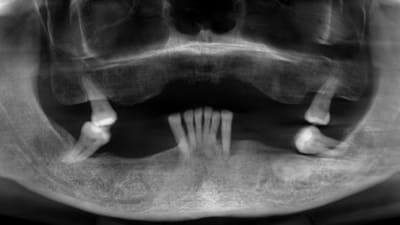

Case Reports Oral Surgery Implantology Ridge Augmentation in a Site of a Previous Implant Failure Using Tenting Screws With Allograft and Collagen Membrane By Daniela Gurpegui Abud, DDS, Dennis P. Tarnow, DDS, Jaffer A. Shariff, DDS March 01, 2022 15 min read